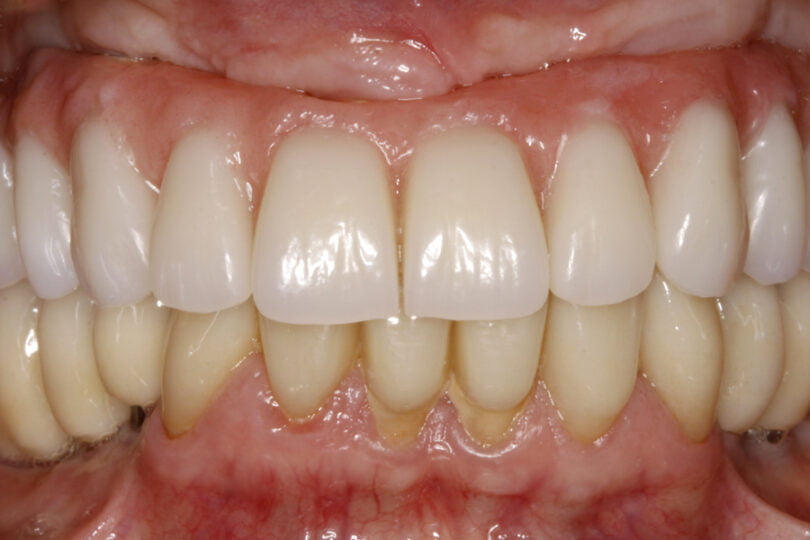

As seguintes imagens apresentam um dos casos incluídos no estudo (figura 03 – 15).